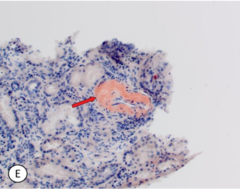

CAA microscopically

Front

leptomeningeal and cortical areas will show accumulations of eosinophilic material will see loss of vascular smooth muscle and double barreled contour apple-green bifringence of amyloid under polarizing illumination or protein immunohistochemistry

Back